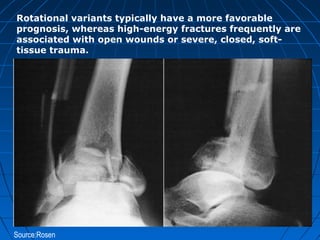

Source:Rosen

Rotational variants typically have a more favorable

prognosis, whereas high-energy fractures frequently are

associated with open wounds or severe, closed, soft-

tissue trauma.